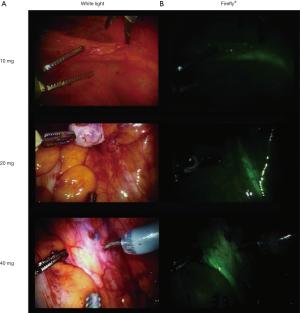

The utility of IS-001 for ureter visualization in humans has been investigated by Farnam et al. (20) In this study, NIR fluorescence imaging of the ureters was evaluated in 24 women during a robot-assisted minimally-invasive hysterectomy. Patients received an intravenous dose of 10, 20 or 40 mg IS-001 before the robotic endoscope was inserted into the abdomen. After administration, fluorescence of the ureters was observed in all patients when imaged with the da Vinci® Surgical System Firefly® imaging system (Figure 4). The strongest signal was observed 10 minutes after patients received 40 mg IS-001 and was therefore considered the optimal dose for ureter visualization. However, the signal intensity decreased rapidly over time. After 60 minutes post injection (or last possible time-point if the operating time was less than 60 minutes), a high fluorescent intensity was observed in only one of the eight patients who received 40 mg IS-001 and in none of the patients who received 10 or 20 mg IS-001. No adverse events, related to IS-001, were reported during the study. Moreover, pharmacokinetic analysis also showed that intravenous administration of IS-001 up to 40 mg was safe and well tolerated.

ZW800-1 and IS-001 are the first experimental dyes with a selectively renal clearance pattern, that have been investigated in humans. de Valk et al. (19) showed that ZW800-1 provides a large safety window in which a single low dose of ZW800-1 (1.0–2.5 mg) is sufficient for intraoperative ureter visualization and real-time assessment of ureter function, even with overlying tissue, permitting precise structural ureter delineation for a period of at least two hours after administration. Moreover, it works on most available commercial imaging systems (e.g., Olympus®, the da Vinci® robot, Stryker® and the FLARE® MIS system). In addition, Farnam et al. (20) investigated the use of IS-001 and showed that the compound is apparently safe and observed the strongest fluorescent signal after an injection of the highest dose of 40 mg IS-001 when imaged with the da Vinci® Surgical System’s Firefly® setting. The duration of the signal strength was shorter compared to ZW800-1 with a decrease in signal intensity already noted at 30 minutes after injection of 40 mg IS-001. This suggests that ZW800-1 has more favorable properties compared to IS-001.